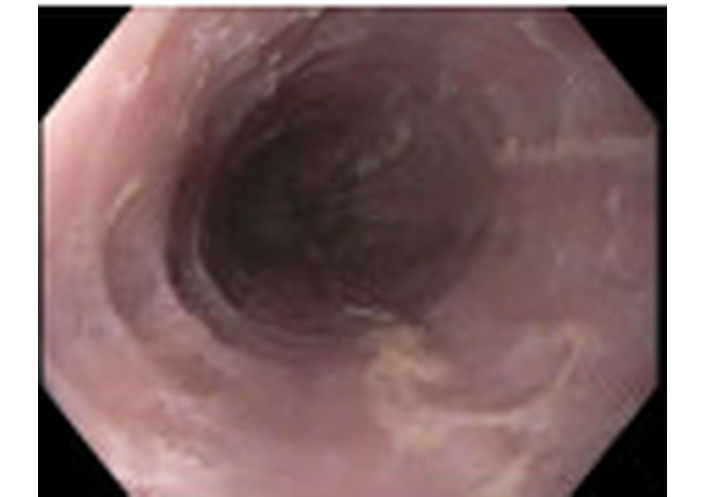

He was empirically treated with omeprazole 20 mg daily for eight weeks and a five-day course of prednisolone 15 mg/mL daily, which resulted in improvement of symptoms. Due to the clinical presentation and history suggestive of esophageal inflammation, he was referred to gastroenterology and underwent EGD. Endoscopy demonstrated Los Angeles Grade B reflux esophagitis without bleeding. Multiple biopsies were obtained. Histopathology demonstrated viral cytopathic changes consistent with HSE (Figure 1) and eosinophil-predominant inflammation consistent with EoE (Figure 2). EGD also demonstrated Los Angeles Grade B reflux esophagitis without bleeding (Figure 3 and Table 2). Diagnosis of HSE was made morphologically based on characteristic herpesvirus cytopathic effect on hematoxylin and eosin staining; HSV immunohistochemistry (IHC) and polymerase chain reaction (PCR) were not performed. Acyclovir 400 mg five times daily for ten days was initiated for antiviral therapy for HSE with a plan for subsequent management of EoE with omeprazole 20 mg daily following control of the viral process. Unfortunately, after initiation of EoE treatment, the patient was lost to follow-up.

Esophagogastroduodenoscopy demonstrated Los Angeles Grade B reflux esophagitis without bleeding.